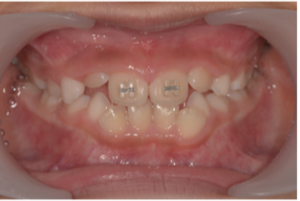

ちなみに受け口な7歳の女の子は現在プレオルソと部分矯正でここまで改善しています☺️

現在

上の前歯2本がだいぶ前方に誘導されているのが分かると思います。

この子は低位舌といい、舌で下の前歯を押すような位置に舌をいつも置いています。プレオルソとあいうべ体操で舌のポジションも改善中です✨